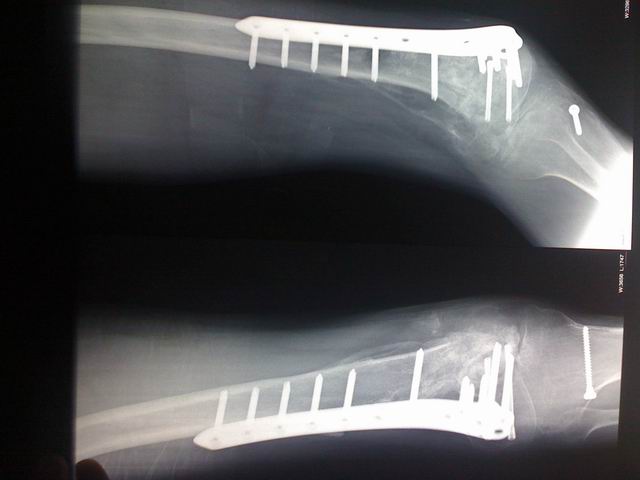

昨晚手术以后的照片。

调整大小 CIMG3526.JPG

调整大小 CIMG3528.JPG

调整大小 CIMG3529.JPG

此番淮南行让我毕生难忘。昨天下午三点弟弟进入手术室,四点四十五推出来。手术是顺利的,螺丝钉钢板全部拔完,还做了膝关节松懈术。昌平院长告诉我只能恢复到20度,还要看后期的锻炼。因为螺丝钉太多,伤口较多,再加上弟弟血功能不是很好,失血很多,当时我都吓坏了。是昌平院长去血库中心调血过来,加上院长和护士们整夜整夜的守护才恢复平静。弟弟现在一切正常,感谢宗亲们的关切和关注。看着昌平院长今天憔悴的样子我都内疚极了,我曾经看到过一句话:哲学是自然科学和社会科学的总和,是分析问题的智慧和方法;人文修养是医生的基本修养,因为医学的本质就是人学。我想说:昌平院长,谢谢您。您是一个德医双馨,文武兼备的好医生。等将来我们手有余力也会像您一样尽心尽力帮助他人,帮助汪氏族人。